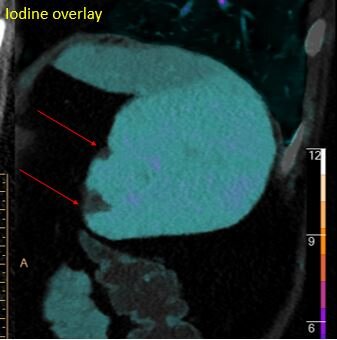

Iodine overlay shows there are actually 2 infarcts present (red arrows).